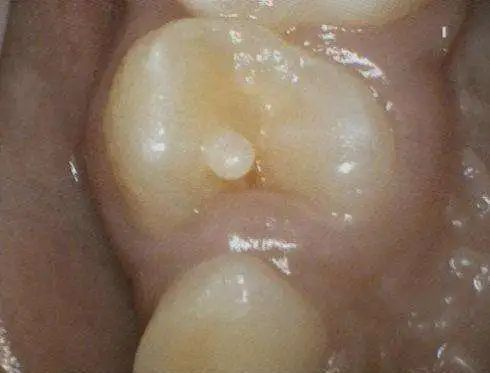

长牙时就要注意

据邵医生介绍,少数人的牙齿上边会凸起一个圆锥形的牙尖,这就是“畸形中央尖”。这种“牙齿上又长小牙齿“的现象常常对称出现,属于一种先天性牙齿发育畸形,受遗传基因控制。

(网络图)

“这些小牙齿和正常的牙齿一样,里边有一根根小管子通向牙神经腔,这些小管子叫做‘牙本质小管‘,可以用来感受冷热、压力。有些人的‘小牙齿‘里还有牙髓组织。“

邵医生说,在牙釉质的保护下,这些牙本质小管和牙髓不会受到太大的刺激,但如果这些小牙齿断裂,牙本质小管和牙髓暴露在外,就会感染发炎,出现牙疼。